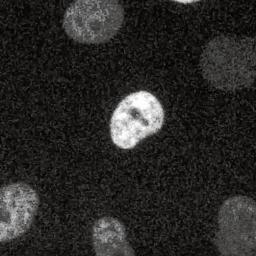

Precisiemedicijn tegen kanker schiet vaak naast

Precisiemedicijnen tegen kanker doden tumorcellen, maar niet zoals bedoeld, waarschuwen Amerikaanse onderzoekers.